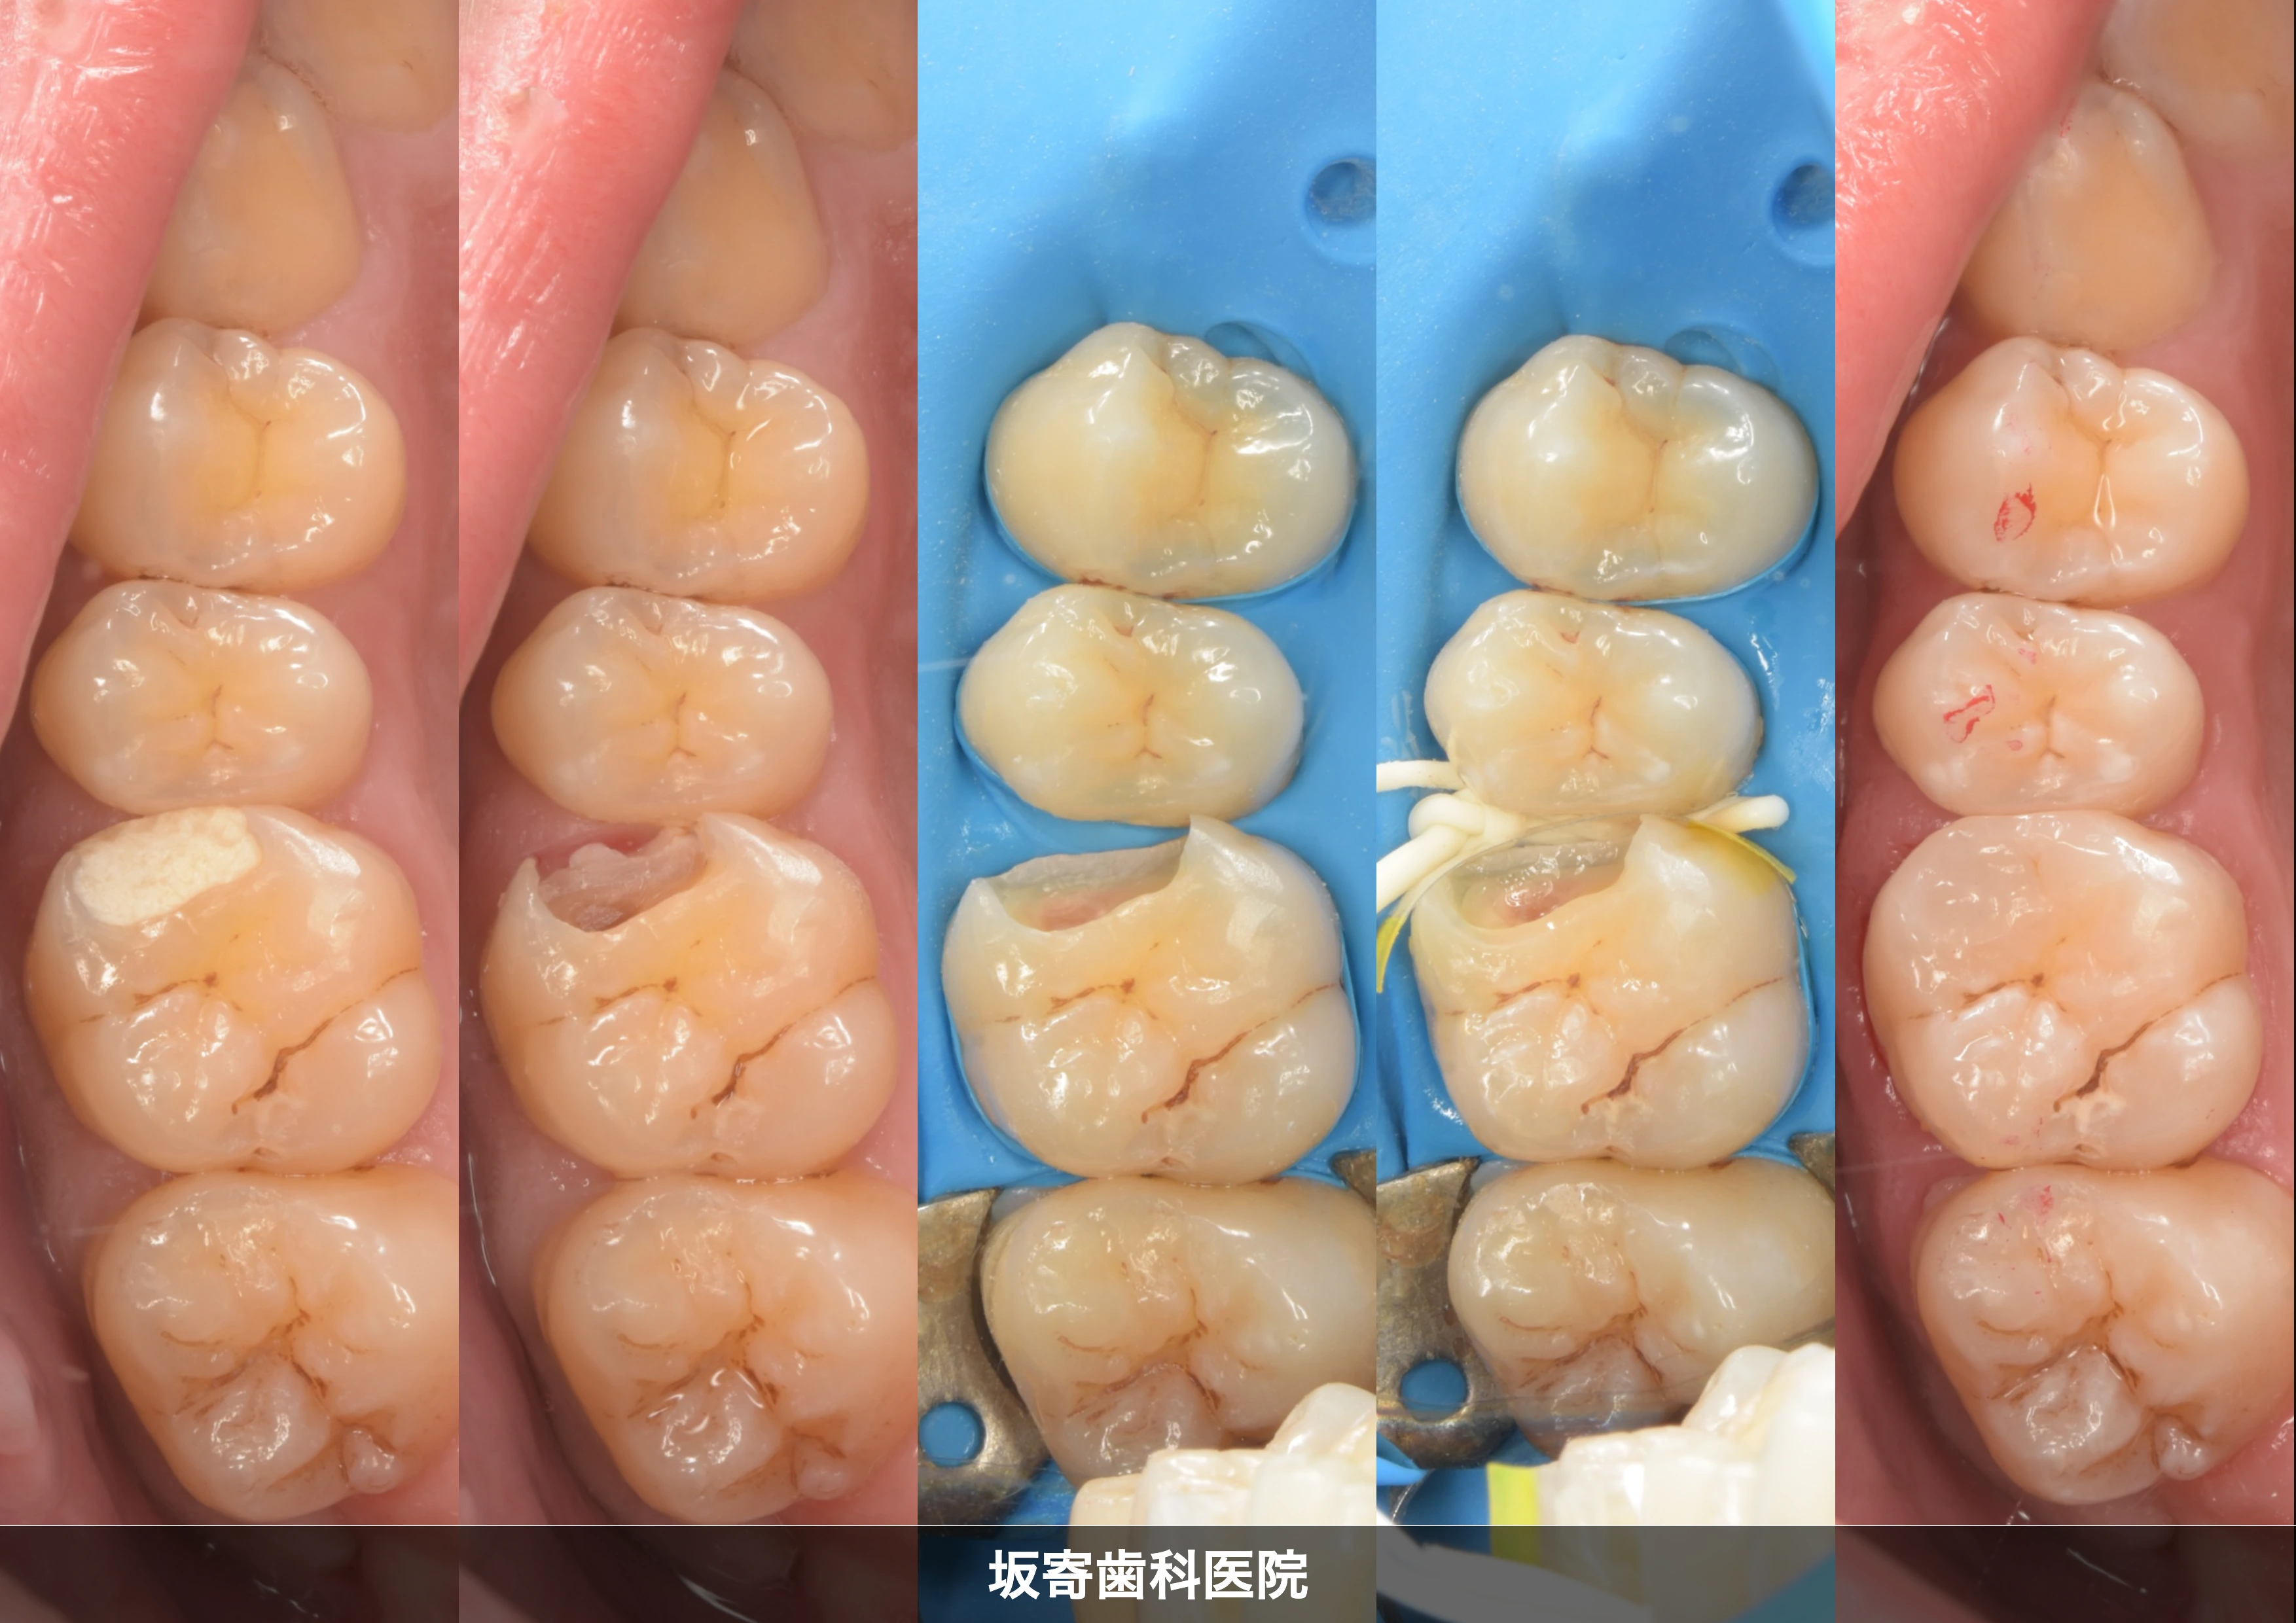

歯質を温存しながら左上の臼歯3本をダイレクトボンディングで修復

東京都内からお越しの30代女性(歯科医師)の患者さんです。経過観察していた左上5番 近心のむし歯が象牙質の半ば(1/2程度)まで進行したため、左上4・5・6番の3本を同日にダイレクトボンディングで修復した症例です。健康な歯質を最大限温存することを優先し、ラバーダム防湿下で精密に接着処理を行いました。

近心クラックから生じた二次う蝕をダイレクトボンディングで修復

東京都新宿区からお越しの40代女性の患者さんです。右上7番 近心のクラック(ひび)を起点に、以前に入っていたインレー(部分的な詰め物)の下でリーケージ(漏洩)が進み、二次う蝕・感染に至っていた症例です。隣接面の接触がしっかりしておりラバーダムが入りにくい条件でしたが、排唾管による防湿で接着環境を確保し、ダイレクトボンディングで修復しました。